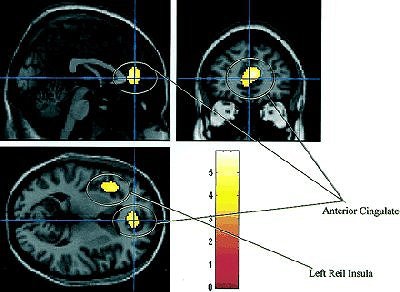

![]() |

| A simple regression analysis between the SPECT images for each subject (and condition) and the NPH scores showed a positive relationship in Brodmann's area 32, corresponding to the anterior cingulate, and the frontal part of the left lobule of the insula of Reil. Image shows two areas most related to clinical improvement from regression analysis. Reprinted with permission from the Society of Nuclear Medicine. Mataró, M; et al, "Postsurgical Cerebral Perfusion Changes in Idiopathic normal pressure hydrocephalus: A Statistical Parametric Mapping of Study of SPECT Images" (J Nucl Med 2003; 44:1884-1889, Fig. 3, p. 1888). |